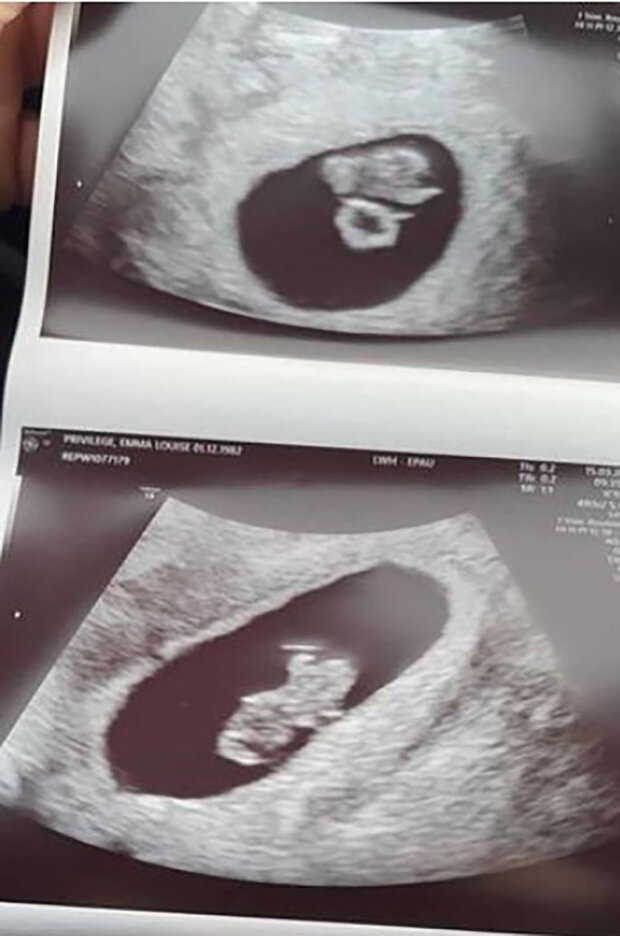

Nakonec byla dvakrát těhotná a dvakrát potratila.

Navzdory zoufalství žena nepřestala pokoušet se otěhotnět, ale potřetí došlo k potratu právě v den jejích narozenin. "Po ztrátě dvojčat jsem pochopila, že je konec. Prostě jsem to nemohla udělat znovu. Joe mi plně rozuměl," prozradila Britka.

O měsíc později zjistila, že nosí čtyři děti. Potíže s těhotenstvím nastaly ve třetím měsíci — po vyšetření lékaři řekli, že opět přišla o své děti.

Nakonec vyšetření ukázalo, že žena čekala dvojčata. V říjnu 2021 se narodily dvě holčičky: Aurora Azalea a Ophelia Lily.